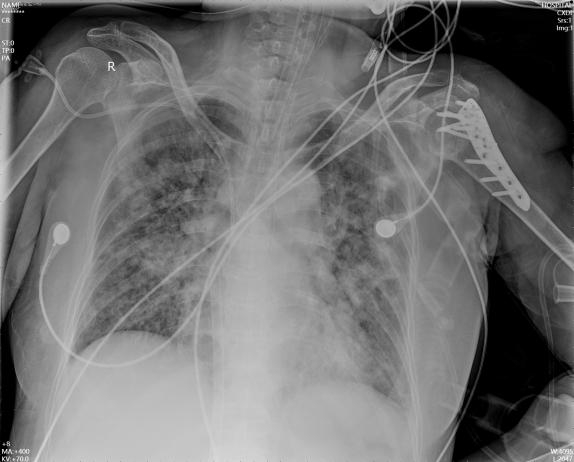

治疗上予以补液、扩容,泵入去甲肾上腺素、间羟胺稳定循环,美罗培南+替考拉宁加强抗感染,祛痰、舒张气道,镇静、镇痛,肺复张、俯卧位通气等治疗; 患者病情进行性恶化,收缩压波动在60~70 mmHg(1 mmHg=0.133 kPa),SpO2波动在70%~80%左右,PaO2最低49 mmHg。11月25日22:40右侧股静脉、股动脉穿刺置管,行静脉-动脉体外膜肺氧(venous-arterial extracorporeal membrane oxygenation, VA-ECMO)治疗(ECMO参数:转速2 300 r/min,血流量3 L/min,氧流量4 L/min,氧浓度1.0),患者血压较前改善130/80 mmHg,但出现上半身发绀,右上肢SpO2 75%左右; 查右桡动脉血气:PaCO2 44 mmHg,PaO2 38 mmHg,SO2 78%; 中心静脉血氧饱和度52%; 遂充分消毒、铺巾,在经食道超声引导下增加股静脉导管置管深度,将股静脉导管尖端送至上腔静脉(图 2所示),患者右上肢SpO2由75%逐渐上升至88%,复查右桡动脉血气分析:PaCO2 46 mmHg,PaO2 55 mmHg,SO2 88%; 中心静脉血氧饱和度66%。继续予以保护肺通气(潮气量6 mL/Kg,平台压25 cmH2O)、俯卧位通气、抗感染、化痰、抗凝及营养支持等治疗; 2022-12-15复查床边胸片提示双肺感染较前好转; 调节呼吸机参数(模式V-SIMV,FiO2 0.5,RR 15次/min,VT 480 mL,PEEP 5 cmH2O),减少ECMO流量至1.5 L/min; 2 h后查右桡动脉血气分析:pH 7.44,PaCO2 46 mmHg,PaO2 98 mmHg,SO2 99%; 于2022-12-15 15:00成功撤离ECMO。患者多次床边胸片见图 3~5。

| 图 3 患者2022-11-27床边胸片 |